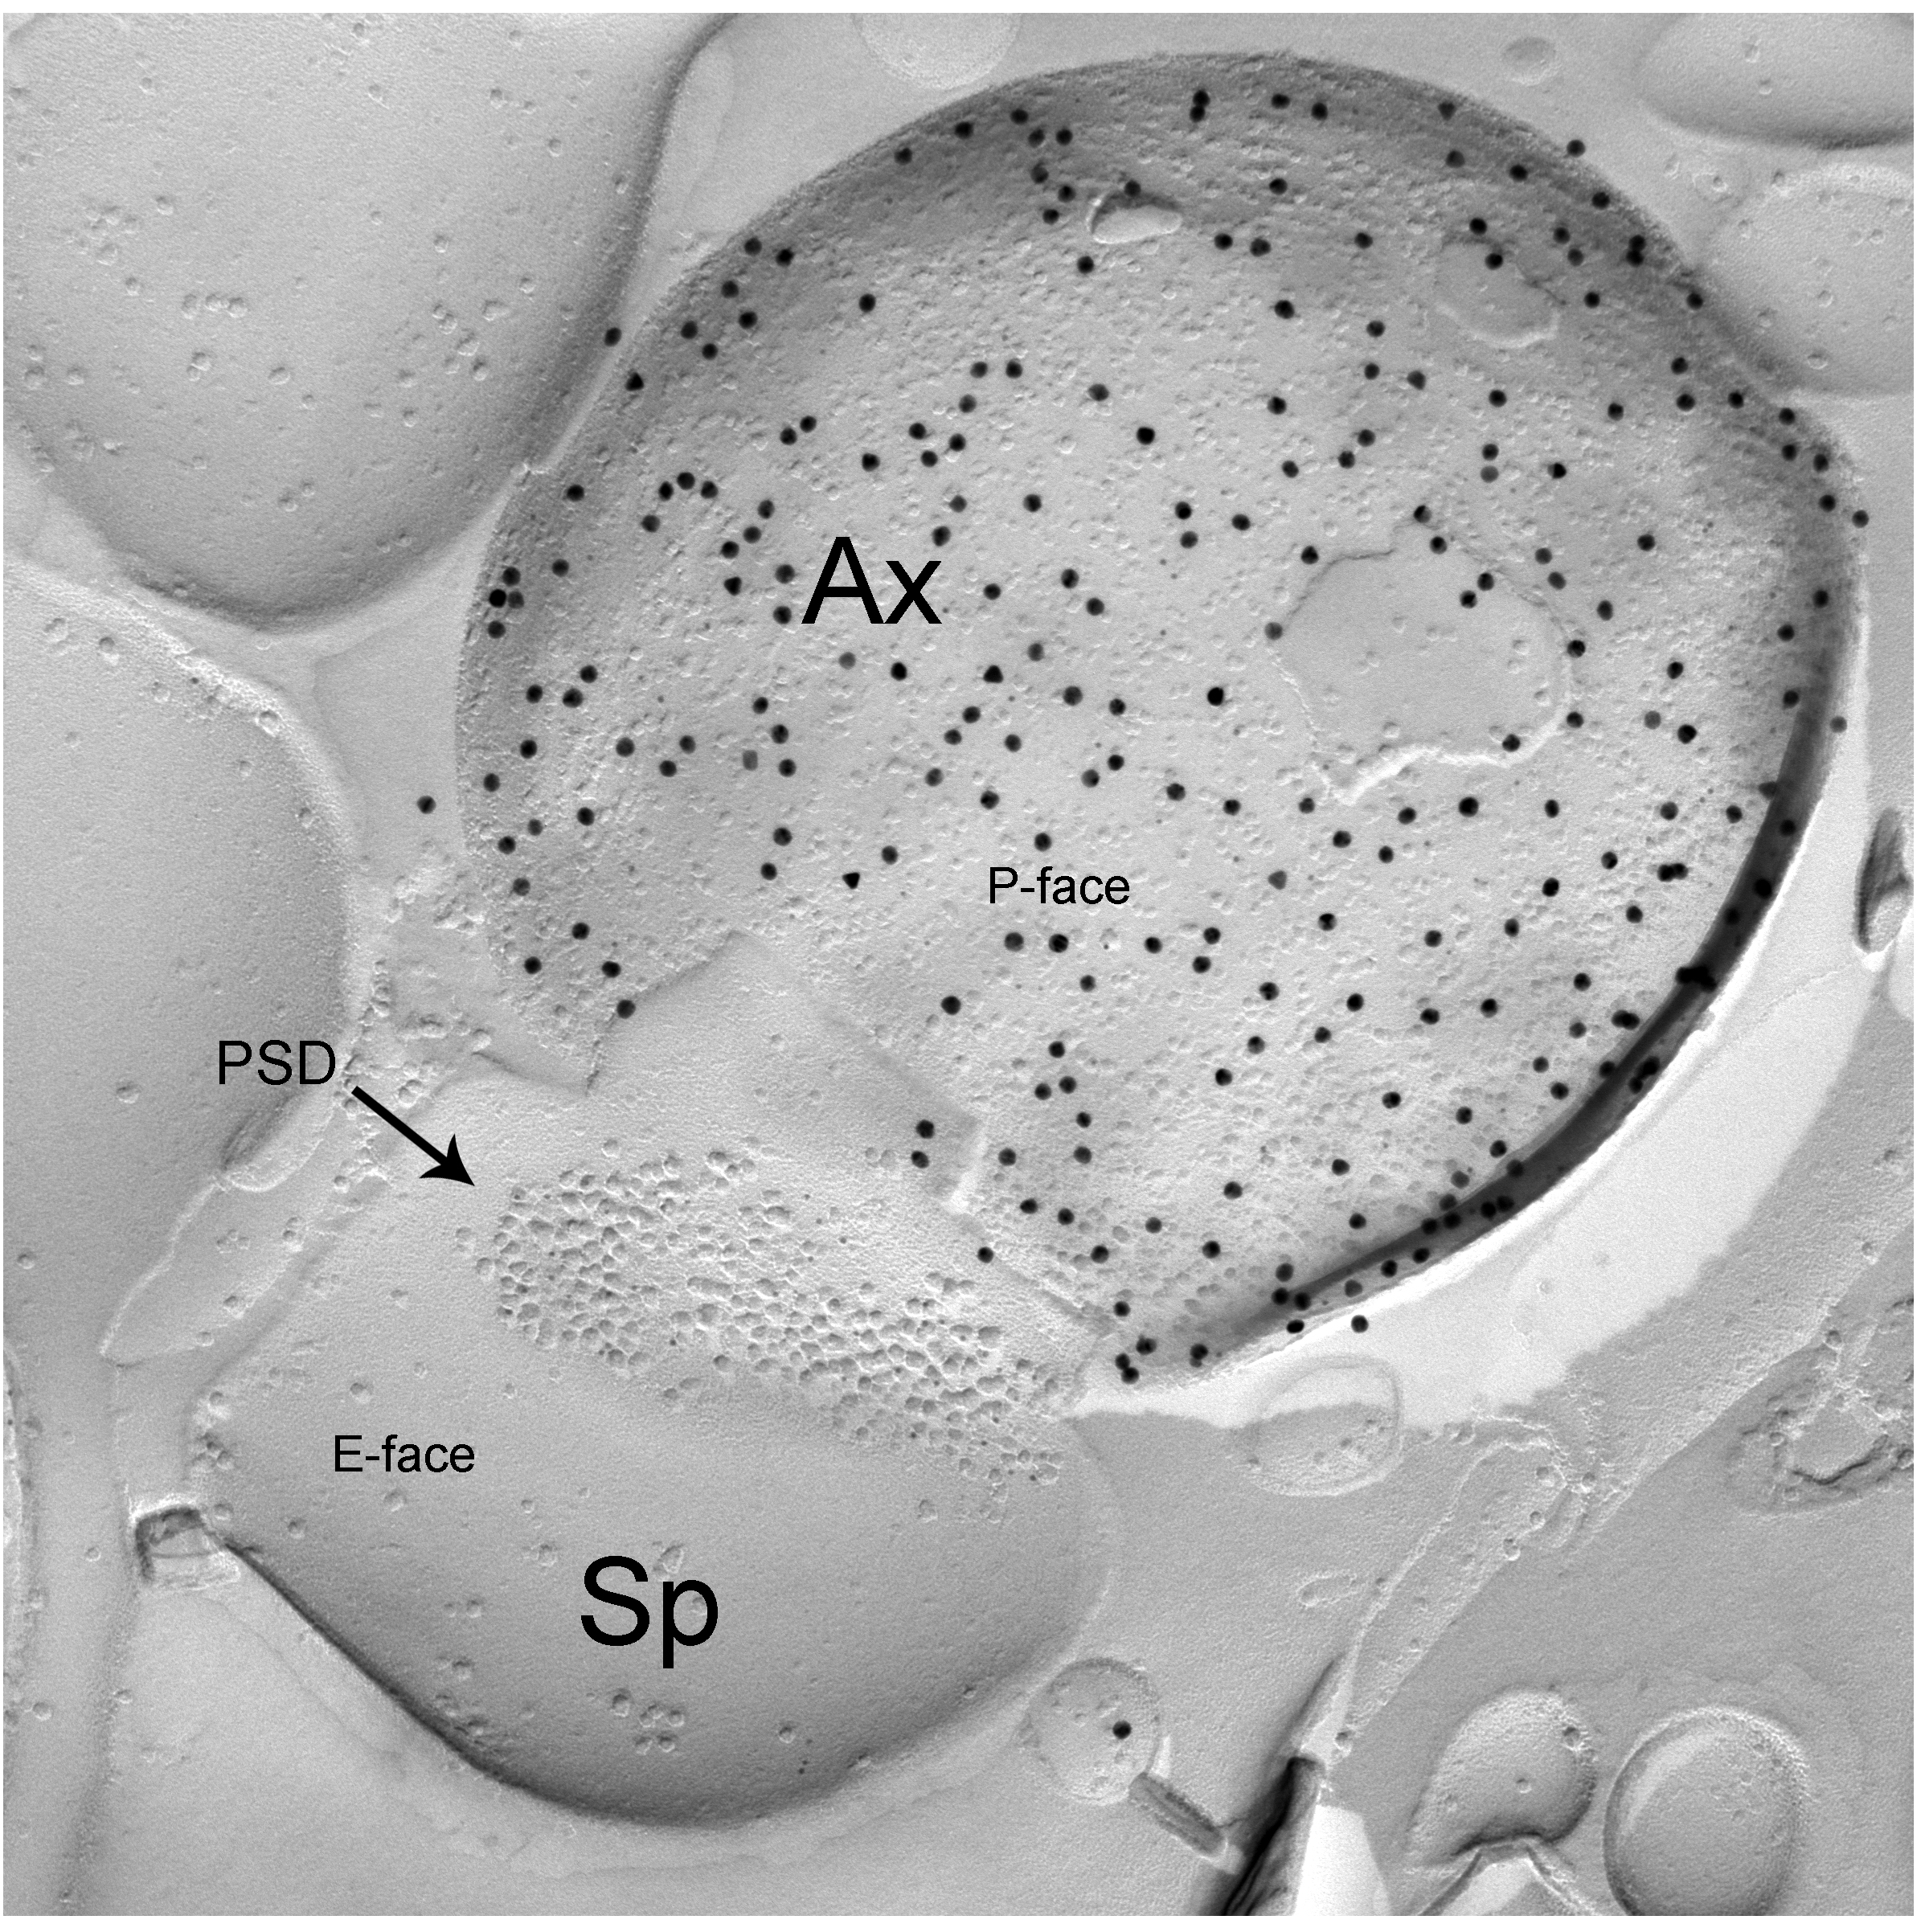

Taking advantage of recent developments in molecular genetics, viral trans-synaptic tracing and novel ultrastructural techniques (e.g. freeze-fracture replica immunogold labelling or FRIL), we investigate long-range connections between amygdala GABAergic neurons (e.g. interneurons of the BLA or ITC) and cortical or subcortical brain structures.